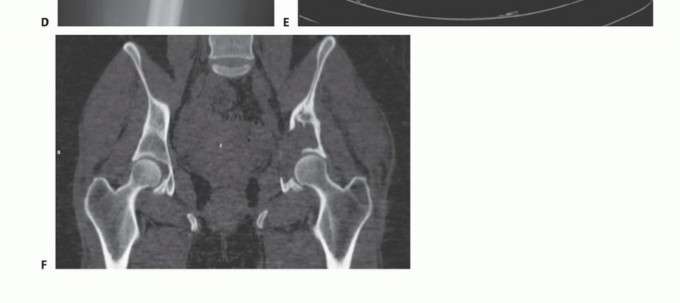

في بعض الأحيان، قد لا تؤثر هذه النقائل على استقرار ووظيفة الحوض بشكل مباشر، خاصة إذا كانت في مناطق مثل عظم الحرقفة أو العانة. ومع ذلك، فإن الأورام التي تصيب الجزء الخلفي من عظم الحرقفة قد تهدد سلامة المنطقة العجزية القطنية، بينما تلك التي تصيب التجويف الحقي (الحُق) يمكن أن تضعف بشكل كبير وظيفة مفصل الورك وقدرة الطرف السفلي على تحمل الوزن، مما يستدعي تدخلًا جراحيًا دقيقًا ومخططًا بعناية.

يُعد الأستاذ الدكتور محمد هطيف، بخبرته الواسعة التي تتجاوز 20 عامًا ودقته المتناهية في جراحة العظام، الرائد الأول في علاج نقائل الحوض في صنعاء واليمن. بصفته أستاذًا في جامعة صنعاء، يتبنى الدكتور هطيف منهجًا شاملاً يركز على استعادة وظيفة المريض وتخفيف الألم وتحسين نوعية حياته، باستخدام أحدث التقنيات الجراحية وأفضل الممارسات العالمية. يُدرك الدكتور هطيف أن الأورام اللحمية الأولية والأورام النقائلية غالبًا ما تتمدد بشكل كبير إلى الأنسجة الرخوة المحيطة، ولكن نظرًا لحساسيتها المتأصلة للعلاج الإشعاعي، فإن الإدارة الجراحية للآفات النقائلية لا تتطلب بالضرورة استئصالًا كاملاً للعضلات المغطية، حيث يمكن معالجة البقايا المجهرية بالإشعاع المساعد بعد الجراحة. يتطلب التشريح المعقد للحوض تخطيطًا تفصيليًا قبل الجراحة، وتحديدًا لتقنية التعرض وإعادة البناء، وتنفيذًا دقيقًا ومتقنًا للإجراء الجراحي لضمان أفضل النتائج للمريض.

- التصوير المقطعي المحوسب (CT Scan): يوفر صورًا مقطعية مفصلة للعظام والأنسجة الرخوة، ويساعد في تحديد حجم الورم، مدى انتشاره داخل العظم، وعلاقته بالهياكل المحيطة.

- التصوير بالرنين المغناطيسي (MRI): يُعد الأداة الأكثر حساسية لتقييم الأنسجة الرخوة ونخاع العظم، ويكشف عن النقائل في مراحلها المبكرة، ويحدد مدى انتشار الورم في القناة الشوكية أو الأعصاب.